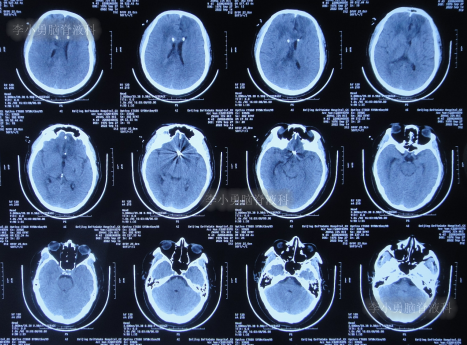

入院时头颅CT示脑室扩张,动脉瘤栓塞术后(图-11)。

图-11:入院时头颅CT

入院后次日进行了脑室外引流术(图-12)。

图-12:2022年8月25日术后头颅CT

脑室外引流术后2天即2022年8月27日,引流出脓性脑脊液(图-13)。

图-13:2022年8月27日

脑室外引流术后4天即2022年8月29日,患者出现意识差,查头颅CT示左侧脑室仍扩张(图-14)。

图-14:2022年8月29日头颅CT

当天给予了左侧脑室外引流术,术后当天查头颅CT示脑室内有2根管(图-15);术后脑脊液化验出真菌。

图-15:2022年8月29日术后头颅CT

2022年9月14日(住院治疗21天),体温变正常,查头颅CT示双侧脑室均变小(图-17)。

图-17:2022年9月14日头颅CT